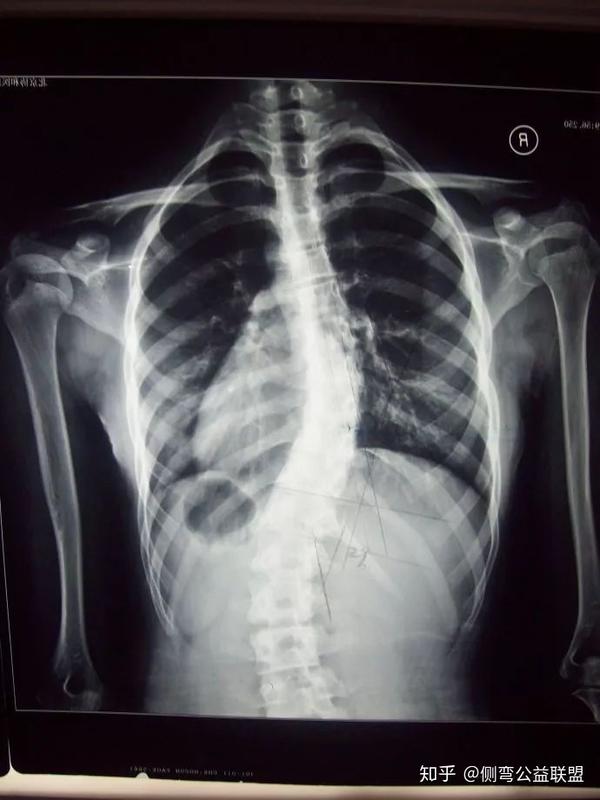

脊柱侧弯x光,脊柱侧弯x光图片

脊柱侧弯患者的x光图像.